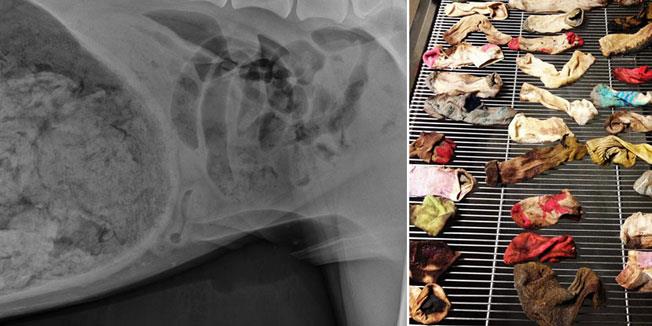

Pas je poslat na rendgen koji je pokazao prisustvo "stranog tela" u stomaku. Nakon dvočasovne operacije, dr Ešli Megi je otkrila uzrok bolova: pas je naime progutao ni manje, ni više nego 43 čarape.